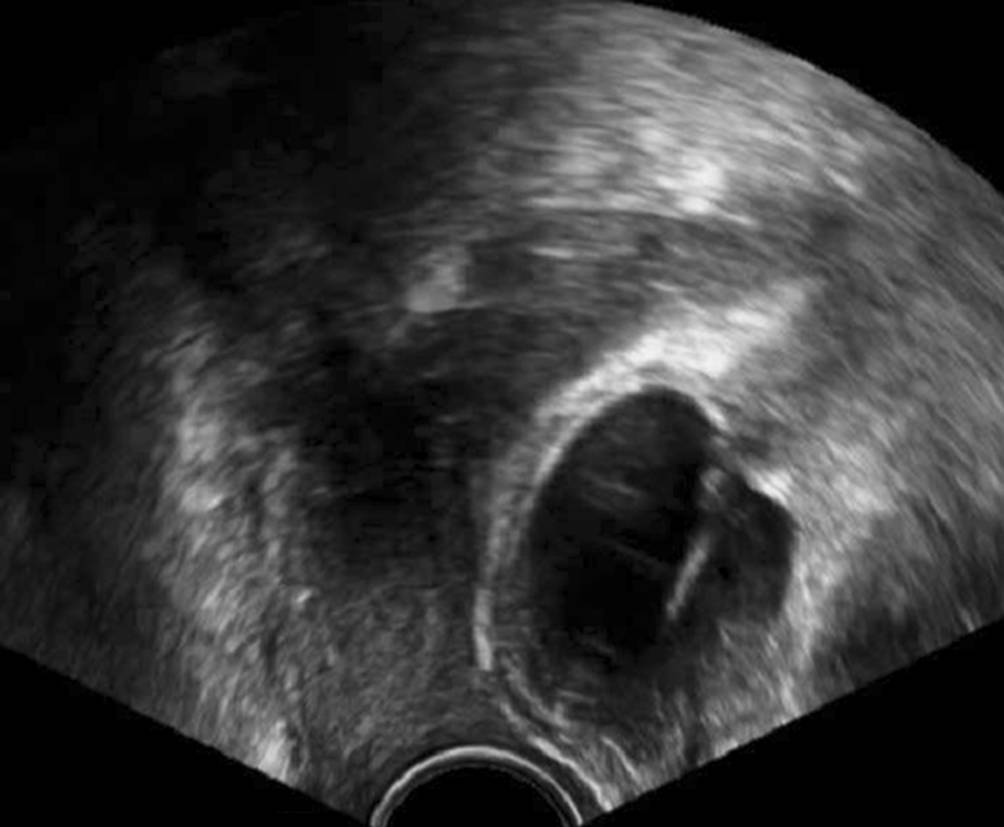

Abb. 5

Mit dem Abdominalschallkopf von perineal geschallte, seit 4 Jahren konstante Gartner-Gang-Zyste im Bereich des Fornix vaginae